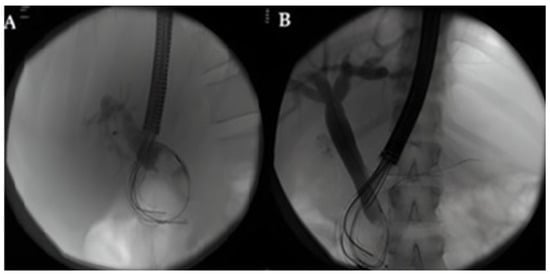

- Rivallin, P.; Lorenzo, D.; Hedjoudje, A.; Prat, F. Single-use duodenoscopes are an efficient tool for emergency ERCP in real life. Endosc. Int. Open 2022, 10, E1497–E1500. [Google Scholar] [CrossRef] [PubMed]